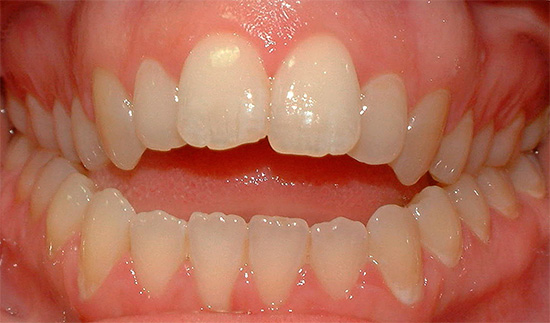

Nota come la forma della mascella cambia dopo il trattamento per un morso distale:

Morso mesiale